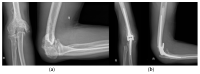

Osteoarthritis is a degenerative condition affecting the whole joint with the underlying bone, representing a major source of pain, disability, and socioeconomic cost worldwide. Age is considered the strongest risk factor, albeit abnormal biomechanics, morphology, congenital abnormality, deformity, malalignment, limb-length discrepancy, lifestyle, and injury may further increase the risk of the development and progression of osteoarthritis as well. Pain and loss of function are the main clinical features that lead to treatment. Although early manifestations of osteoarthritis are amenable to lifestyle modification, adequate pain management, and physical therapy, disease advancement frequently requires surgical treatment. The symptomatic progression of osteoarthritis with radiographical confirmation can be addressed either with arthroscopic interventions, (joint) preservation techniques, or bone fusion procedures, whereas (joint) replacement is preferentially reserved for severe and end-stage disease. The surgical treatment aims at alleviating pain and disability while restoring native biomechanics. Miscellaneous surgical techniques for addressing osteoarthritis exist. Advanced computer-integrated surgical concepts allow for patient personalization and optimization of surgical treatment. The scope of this article is to present an overview of the fundamentals of conventional surgical treatment options for osteoarthritis of the human skeleton, with emphasis on arthroscopy, preservation, arthrodesis, and replacement. Contemporary computer-assisted orthopaedic surgery concepts are further elucidated.